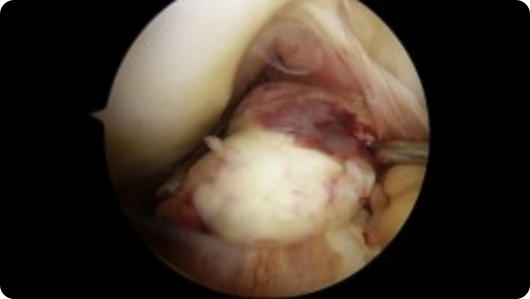

Arthroscopic image of a rotator cuff tear Arthroscopic image of a repaired rotator cuff

Rotator Cuff Tear

Rotator Cuff Repair